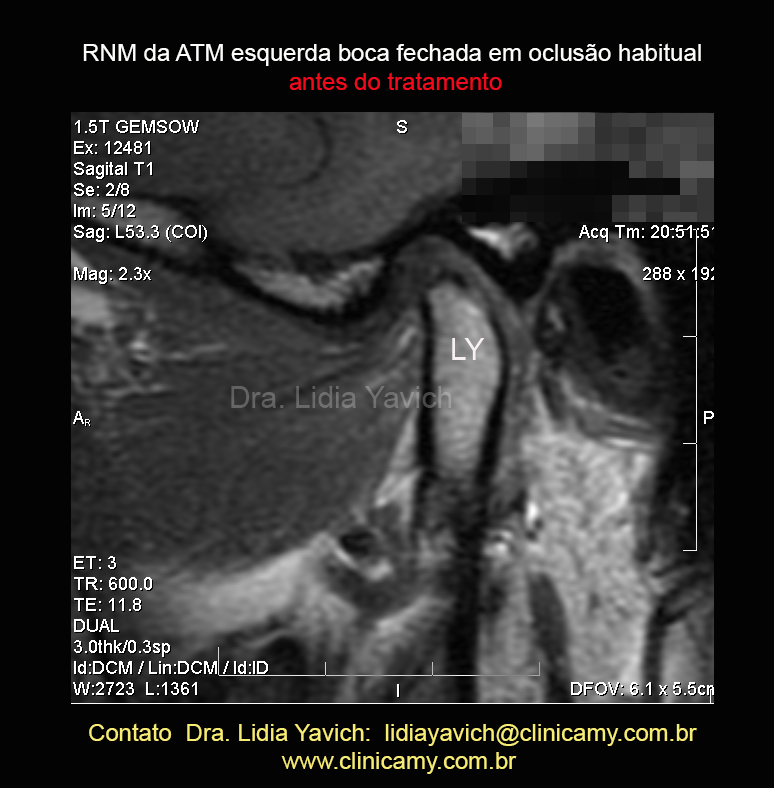

RNM: corte sagital,boca fechada ATM esquerda.Esta imagem não mostra alterações significativas.

Este outro corte sagital mais interno da RNM da ATM esquerda em boca fechada mostra compressão e retroposição do côndilo mandibular. Observa-se uma faceta superior na cabeça mandibular.

LEMBREMOS QUE estamos olhando uma imagem bidimensional e que temos que entender que a COMPRESSÃO É TRIDIMENSIONAL.